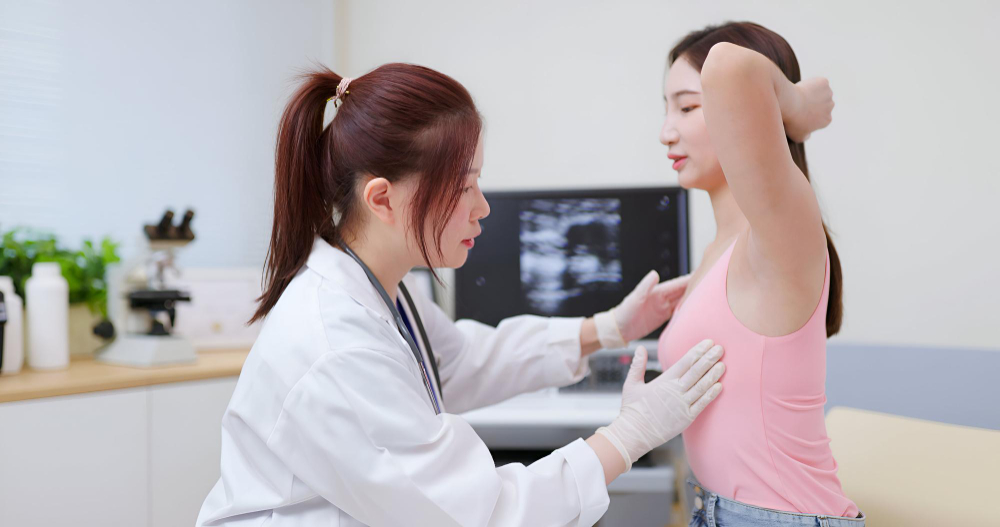

What is Fibroadenoma? Fibroadenoma is a common, non-cancerous breast lump. Many women find these lumps during self-exams or routine check-ups. Usually, fibroadenomas feel smooth, firm,

What is Cervical Cancer? Cervical cancer is a type of cancer that starts in the cervix. The cervix is the lower part of the uterus